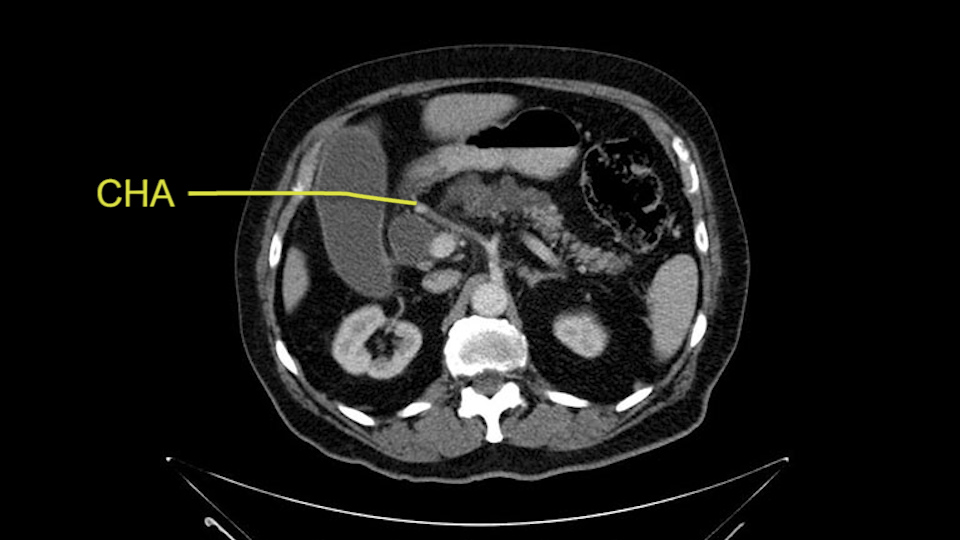

He has no liver metastases or obvious metastatic disease. On reviewing his CT scan, he has normal vascular anatomy; he has no involvement of the portal vein by the looks of it, or the superior mesenteric vein.

He has normal arterial anatomy: no accessory or replaced right hepatic artery, which is important because sometimes the right hepatic artery can come behind the neck of the pancreas and you have to be careful of that in a Whipple dissection.

Then you look for anomalies. The one you worry about the most doing a Whipple is a replaced or aberrant right hepatic artery coming off the SMA at its origin. So again, find the SMA. You can find it because the renal vein goes through it. Follow it up, up-up-up. Nothing coming off of there that I can see here. Nothing coming off of it, nothing coming off of it and just to confirm it, look at the celiac trfurcation. There’s the celiac, there’s the bifurcation, there's the splenic artery, hepatic artery. Make sure there’s a right, which there is here. The right usually goes under the bile duct: important when you’re going around the bile duct to do a Whipple. A replaced right goes under the portal vein and the bile duct way over here on the right. That’s about it.

To plan a pancreatoduodenectomy, we start by reviewing the vascular anatomy, especially the origin of the celiac trunk, here, in front of the aorta, looking for any evidence of stenosis. In addition, we look at the origin of the superior mesenteric artery, to look for any branches, and any replaced right hepatic arteries coming from the superior mesenteric artery; which does occur in about 12% of the population.

The second point about the vascular anatomy-, is to again look for right hepatic arteries in the hilum, coming from the superior mesenteric artery by palpating-through the Winslow Hiatus. Usually we will check for a pulse in the posterior aspect of the hepatic hilum, where a right hepatic artery should not usually be found. In this case, the precaution is to avoid an accidental ligation of the right hepatic artery that might jeopardize perfusion of the right lobe, or if there is a completely replaced hepatic artery that can put the liver circulation at risk.